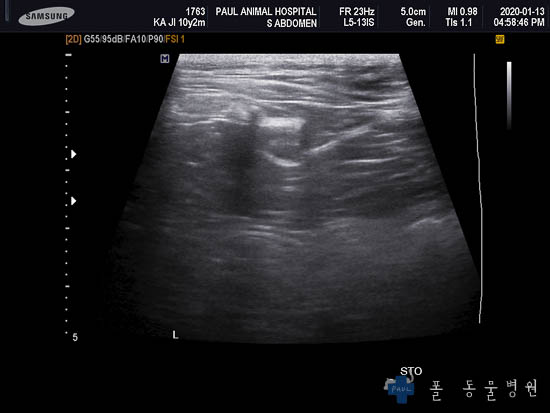

다음은 복부의 장기를 더 자세히 평가할 수 있는 초음파 검사 결과입니다.